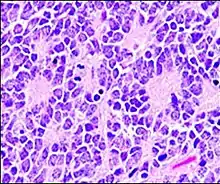

Structure of a Homer Wright pseudorosette

A Homer Wright pseudorosette is a type of pseudorosette in which differentiated tumor cells surround the neuropil.[15] Examples of tumors containing these are neuroblastoma, medulloblastoma, pinealoblastoma, and primitive neuroectodermal tumors of bone. Homer Wright rosettes are considered "pseudo" in the sense that they are not true rosettes. True rosettes are Flexner–Wintersteiner rosette, which contain an empty lumen. Homer Wright rosettes contain abundant fibrillary material. They are named for James Homer Wright.

Homer Wright pseudorosette